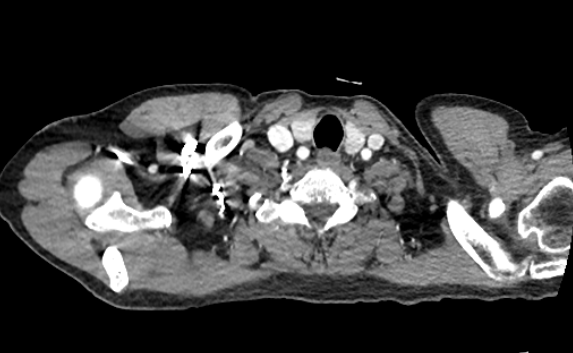

CT Lung

CT Lung CTA

CT Abdomen

CT Abdomen MRI Spine